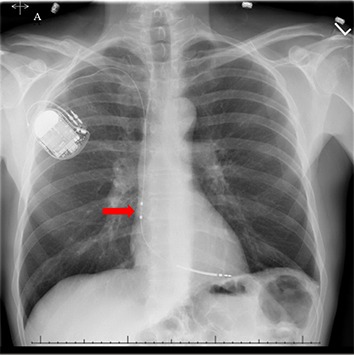

Dx ICD - Avoid problems with atrial lead, but reap benefits of atrial signal ?

dx_icd.jpg